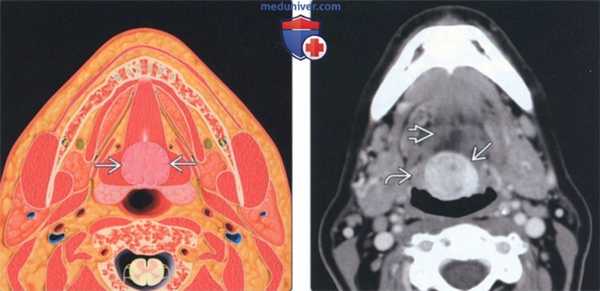

(Слева) На аксиальном рисунке изображена язычная щитовидная железа в задних отделах языка по средней линии, непосредственно глубже слепого отверстия. Четкие контуры и срединное расположение в области дна полости рта или в основании языка - типичные признаки язычной щитовидной железы.

(Справа) На аксиальной КТ с КУ в основании языка по средней линии определяется округлое контрастирующееся образование с четкими контурами, с минимальной деформацией подбородочно-язычных мышц. Плотность язычной щитовидной железы намного выше по сравнению с минимально контрастирующейся язычной миндалиной.